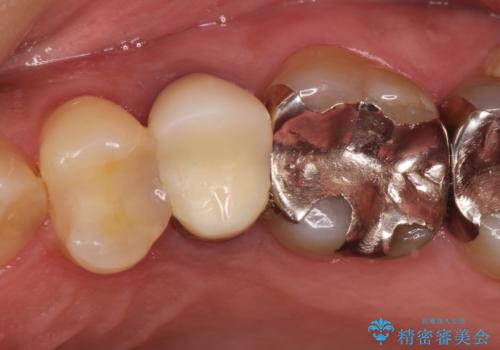

- 左上の後ろから3番目の歯のかぶせ物が適合不良であったので、根管治療を行い、オールセラミックを装着する計画としました。

またその隣の目立つ銀歯も同時に、セラミックに交換することとしました。